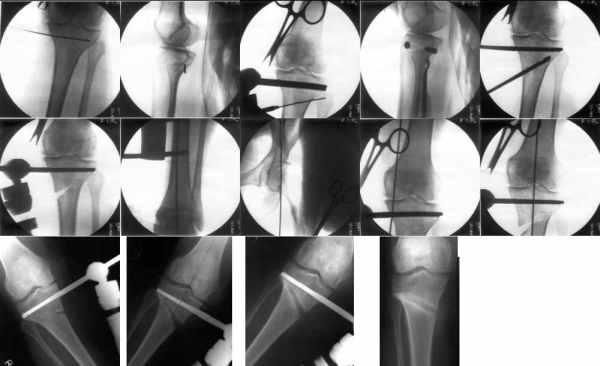

Yesterday one leg was done (my plan to make both in one session were cancelled because of external reasons). So much exciting and useful experience.

The osteotomy line i planned to make a bit oblique, but not so as you suggested. But at the moment of osteoclasis after corticotomy through the anterior stab wound the line became almost as you described. Now problem is how to reproduce thee line at the next leg ;-)

The prominent fragment seems to be useful for cosmetic purposes, because aesthetic guys perform medialization of the distal fragment to gain attractive curve at the medial side of the leg. Also all locking options became available - initially i planned to engage only two most

proximal 45 degree holes.

I cut the fibula because i externally rotated the distal fragment by 6-7 degrees. With only angular correction it didn't show any displacement.

Today CT for estimation of rotation was performed, results i will see only tomorrow. Rotation of the operated limb can be corrected with the second surgery. Comments/critics are welcome.

THX to all people discussed the case.

Yesterday i performed correction of one leg (the plan to make both in one session was cancelled because of some external reasons). Suggestions of Nuno Lopes were most close to my view. A small wire distractor was used intraoperatively. Derotation ~6-7 degrees was performed also. CT scans evaluating rotation will be available only

tomorrow. No problem to change rotation of the operated limb in the moment of the second surgery. Comments/critics are welcome.

Can the attached result be analyzed by the software?

Re: Деформация голеней

Как уже писал, вчера сделал одну ногу (может, свой плюс будет что не обе- вдвое меньше травма, сразу на костыли встанет, оперированную ножку немного разомнет, тут и вторую заделаем).

Операция была интересной, много полезного опыта приобрел.

Снимки в приложении - фас сравнительный с неоперированной ногой. Жду критики.

Впрос про остеотомию большеберцовой непраздный. Эта получилась при надломе несколько более наклонно, чем я делал (сейчас проблема,

как на второй ноге сделать так же). Вот этот высоящий "зуб" центрального отломка не заменит ли в плане косметики то, что получается при медиализации дистального?

|

Hi Alex:

Nice job!

It is very interesting to me that as you have derotated the tibia you have centred the patella, I think and the prox tibia looks much more anatomic.

The analysis in the attached images is direct, just using the tools.

Tibial tilt is perhaps more than you want but the tibial correction is to 90 (very slight over

correction.

Will need full length views to tell us about the hka but it appears neutral.

Measurements took 4 mins

Derek